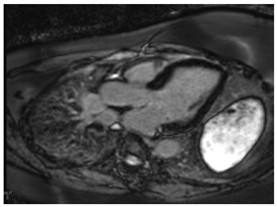

| CMR Parameter | Key CMR Findings | Illustrative Example |

|---|---|---|

| Cardiac Structure and Function |

| ![]() |

| T1 time | Short native T1 time | ![]() |

| T2 Time | Possibly elevated T2 time in the basal inferolateral wall or in areas of LGE | ![]() |

| LGE | Mid-myocardium LGE of the basal inferolateral wall | ![]() |